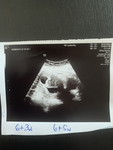

Hello po mga mamshies! Anyone here na may twins? I’m a first time mom po & preggy with twins. Just wanna ask if kelangan ba dalawang crib bibilhin namin or kasya na sila sa isa for a couple of months? Or any suggestion for twins essentials po. Salamat masyado